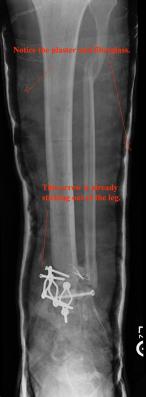

Pre-corrective surgery X-Rays of the damaged right & left legs / ankles

These x-rays were taken at Dr Armendariz’s office, just prior to performing any corrective surgery. As can be seen in these images,

there was no tibia bracing provided by Dr. Keller. Liam was released from Dr Keller’s care with instructions that full weight bearing could

be accomplished within 2 months of Keller’s last surgical procedure. The best example to examine is the second image (from the left) of the

top how. Notice how the bones that should be aligned with the tibia are in fact on the other side of the leg. The third image shows how badly

Liam’s left foot was twisted as a result of the pool placement of the external fixation. What is not obvious is that the screw at the bottom

of the plate on the right fibula missed being screwed into the plate.